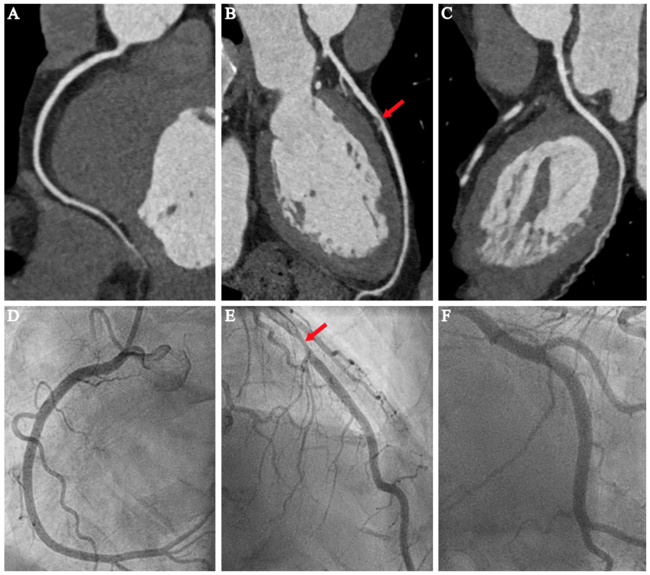

Accuracy of CTCA and potential benefit of CTCA-guided ultraselective ICA. CTCA was accurate in predicting a normal contralateral coronary artery on CTCA to be indeed normal on ICA in 201 patients (99.5%) with CAD limited to the LCA or RCA. In only 1 patient (0.5%), ICA revealed a nonsignificant coronary artery stenosis (30%-50%) in the contralateral coronary artery, not needing further evaluation or intervention. Therefore, in all patients included in this study, a CTCA-guided ultraselective ICA approach would be feasible and could have led to a decrease in procedure time and radiation exposure (Figure 3 and Table 3). If this ultraselective ICA had been used, the mean decrease in procedure time would have been 4.22 ± 2.67 minutes (61 ± 16%). Mean values for potential DAP reduction were 1501 ± 1304 mGy•cm2 (29 ± 13%).